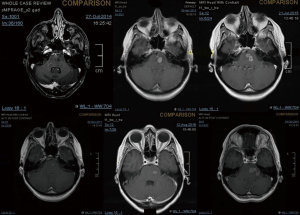

A 43-year-old lady with a past medical history of von Willebrand’s disease, had problems with double vision, nausea and headaches. An MRI of the brain (Figure 3) was performed showing a likely pontine low-grade glioma. Due her past medical history of von Willebrand’s disease and the location of the lesion a biopsy was not possible. The patient was treated with radiotherapy up to 54 Gy in 30 fractions to the visible tumour on MRI. The first follow-up MRI done 2 months after radiotherapy showed an increase in the size of the cystic component of the tumour with new multifocal solid nodular enhancement. Concluding remark stated that the MRI features most likely represented disease progression rather than radiotherapy-related changes. At the same time, the patient had been getting increasing problems with her vision in her left eye, weakness and numbness in her right side and has had a few falls. Neurological examination showed grade 3/5 power loss in her right arm and 4+/5 in her right leg. Because of the behaviour of high-grade glioma, salvage chemotherapy with temozolomide, six cycles every 28 days was planned. She started with dexamethasone as symptomatic treatment as well. During chemotherapy, the patient’s symptoms improved and allowed reduction of the steroids reduction. She completed six cycles of temozolomide and started follow-up with MRI. Eleven months after finishing salvage chemotherapy progressive disease was noted with a new enhancing lesion in the right posterior cerebellum and increase in size and enhancement of the left pontine lesion. Simultaneously, the patient started with slight right leg weakness and headaches at the right side. She started PCV as second-line chemotherapy. Unfortunately, PCV was stopped after two cycles due to neutropenic sepsis and worsening performance status. Six wee4ks later the patient was admitted to hospital with left leg weakness and urinary retention. A spinal MRI (Figure 4) was done, showing multiple cystic and solid intradural lesions in the lumbar spine causing nerve cauda equine compression. The patient was treated with dexamethasone and underwent palliative radiation therapy (8 Gy in single fraction) to the lumbar spine (T12–S5). She was transferred to a palliative care service.

The mechanisms of tumour spread along the central nervous system include perivascular growth; local invasion (choroid plexus, cortical surface and subpial space); and along white matter tracts associated with craniotomies and location of the tumours adjacent or proximal to ventricular structures (6,9,10). In our cases, both were adjacent to ventricular structures at relapse (Figures 2,3F).